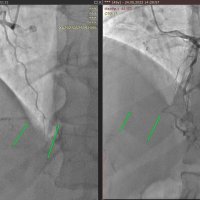

Пациент 45 лет (молодой возраст). На коронарографии – нет кровотока по крупному сосуду артерии сердца (хроническая окклюзия), сектор кровоснабжения артерии очень большой. Остальные артерии сохранены. Клинические проявления стерты, организм временно компенсировал потерю крупного сосуда. Необходимо открывать крупный сосуд сердца, что влияет непосредственно последующую выживаемость и качество жизни.

Пациенту проведена операция через правую лучевую артерию, выполнена попытка прямого (антеградного) восстановления закрытого сосуда, не успешная. Инструменты не могут пробить жесткую бляшку и восстановить проходимость.

Поэтому через левую лучевую артерию выполнен обратный (ретроградный) путь к закрытой артерии с использованием обходных (коллатеральных) сосудов, которые сформировались компенсаторно. Инструменты проведены слева направо, через все сердце, чтобы добраться к закрытому сосуду с обратной стороны. Попытка восстановления выполнена успешна.

Таким образом удалось восстановить просвет закрытой артерии. Далее установлен стент (металлический каркас) с лекарственным покрытием, который будет поддерживать просвет артерии в раскрытом состоянии и запустить прямой (антеградный) кровоток к большому объему сердечной мышцы (миокарду).